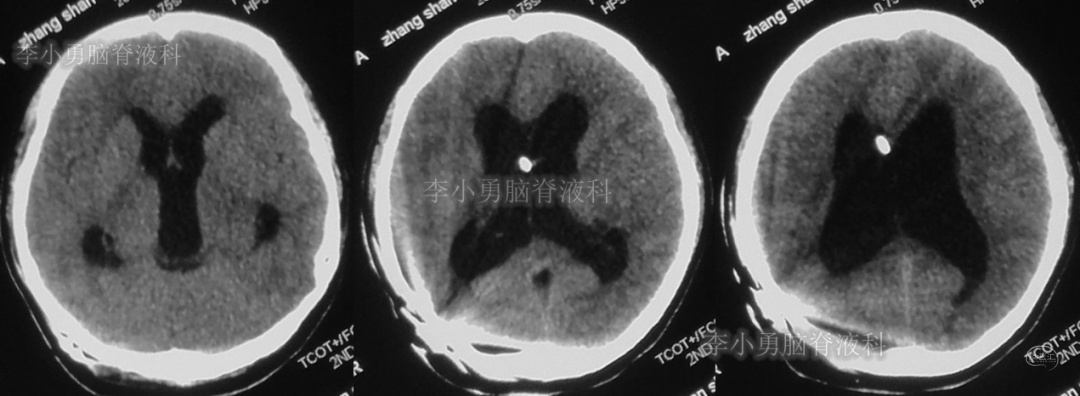

患者于2018年1月29日,突发头痛、头晕、恶心、呕吐,并高热40度。在当地医院门诊输入4天抗生素后发热缓解,但出现了双眼不能上视(眼球不能向上看)。5天后即2018年2月3日,在当地的第1家医院:浙江省海宁市某医院行头颅CT(图-1)发现脑室扩张,当地医院诊断为“梗阻性脑积水”。

图-1:2018年2月3日头颅CT